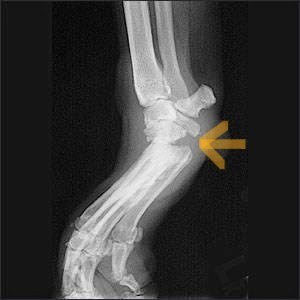

X-rays are recommended to rule out fractures and evaluate surrounding structures, although the diagnosis is often made based on examination findings alone.

Partial Achilles Rupture

Complete Achilles Rupture

X-ray changes with Partial and Complete Ruptures